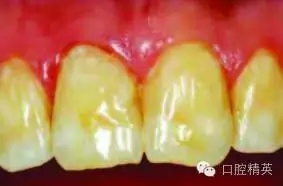

圖2:排齦,去除尖銳和薄弱的釉質(zhì)邊緣

使用330-鎢鋼車針去除尖銳和薄弱的牙釉質(zhì)邊緣,開敞釉質(zhì)洞緣(圖2)。